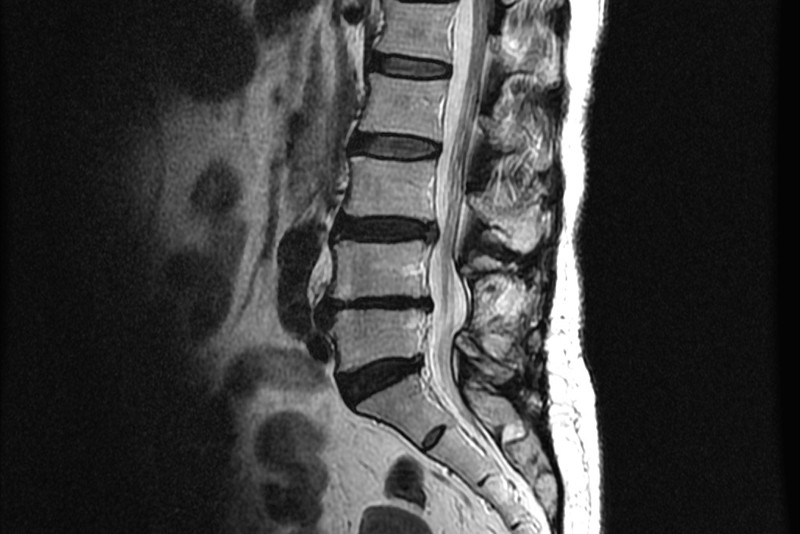

허리디스크는 척추 뼈 사이의 구조인 디스크가 원래의 위치에서 탈출되는 증상을 말합니다. 그리고 허리디스크라고 불리는 경우가 많지만 정확한 병명은 요추 추간판 탈출증이라고 합니다. 따라서 요추 간에 있는 디스크는 탄력성이 높아 외부로부터 신체적 충격을 완화하고 딱딱한 뼈끼리 직접 부딪치는 것을 방지하는데 외부 충격 및 잘못된 자세로 장시간 있을 경우에는 디스크가 튀어나오거나 해서 염증을 일으키고 신경을 자극해 디스크라고 불리는 방사통 및 요통 등의 통증을 일으키는 것이 허리디스크이라고 합니다.

허리디스크의 증상은 허리 통증뿐만 아니라 다리로 내려가는 방사통은 많이 호소하는데 다리 저림, 감각 저하, 근력저하도 나타날 수 있습니다. 디스크의 바깥쪽을 이루고 있는 섬유륜이 찢어지면 디스크의 중앙 부분인 수핵이 찢어진 틈새로 튀어나오게 되는데 이는 디스크가 탈출한 것이고 흔히 디스크가 터졌라고 합니다. 디스크 탈출은 나이가 들면서 나타나는 섬유륜의 퇴행성 변화가 관련이 깊고 허리를 비틀거나 갑작스럽게 숙이는 동작, 외부로부터의 충격으로 인한 외상으로 인해 주로 나타납니다.